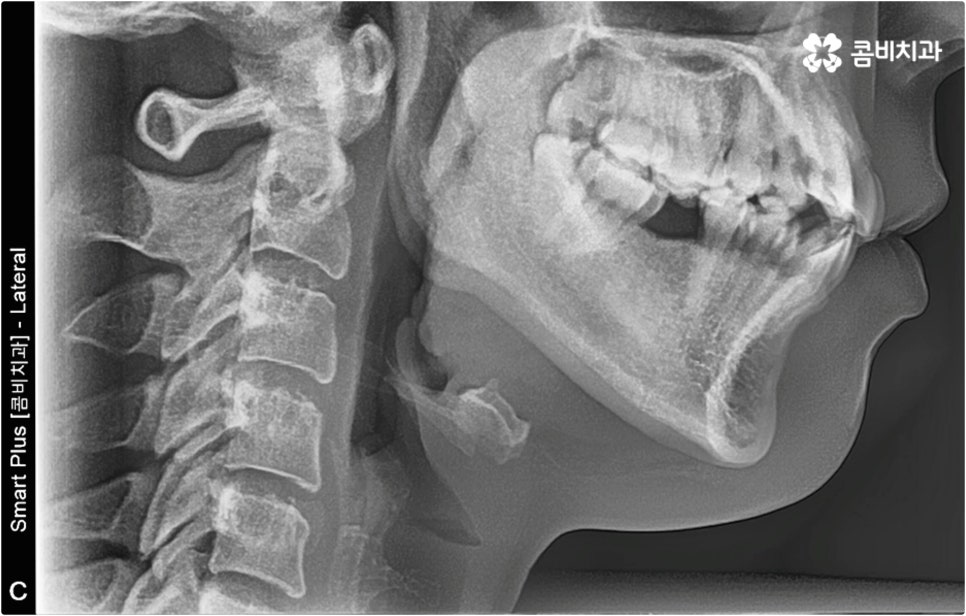

이때 현재 상황을 정밀하게 보여주는 3D CT, 미래 결과를 예측해서 보여주는 모르페우스와 같은 디지털 장비를 통해 전체 플랜을 자세하게 설명해 주고 중간 과정 역시 꼼꼼하게 브리핑해 주는 의료진과 함께 교정 치료를 진행한다면 조금은 길고 힘들게 느껴질 수 있는 전체 교정 과정에 보다 적극적이고 긍정적인 마음으로 임할 수 있을 거예요. 또한 앞서 말씀드린 것처럼 불편함을 줄여줄 수 있는 다양한 교정 장치와 방법 등이 있으니 가능한 선택지 내에서 자신의 상황에 최적화된 장치를 이용해 보시면 여러모로 도움을 받으실 수 있습니다.

이와 같이 치아설측교정 과 콤비교정은 브라켓을 치아 안쪽으로 붙여서 치료하는 방식이기 때문에 굉장히 고난도의 복잡한 교정 치료라고 할 수 있습니다. 교정에 대한 높은 이해도와 해부학적으로 뛰어난 노하우, 풍부한 경험을 통해 축적한 세심한 기술력을 갖추고 있는 의료진에게 치료를 맡기는 것이 중요하며 정밀 디지털 검진 장비를 통한 정확한 검사 결과를 바탕으로 무리하지 않게 진행하실 필요가 있어요. 또한 양치질을 할 때 음식물 제거가 쉽지 않으므로 환자분들 본인이 평상시 신경써서 닦아주시는 것은 물론 꼼꼼한 케어시스템을 통해 주기적으로 관리해 주는 치과에서 교정 치료 및 사후 유지 관리까지 철저하게 받아보시길 권유드리고 있습니다.